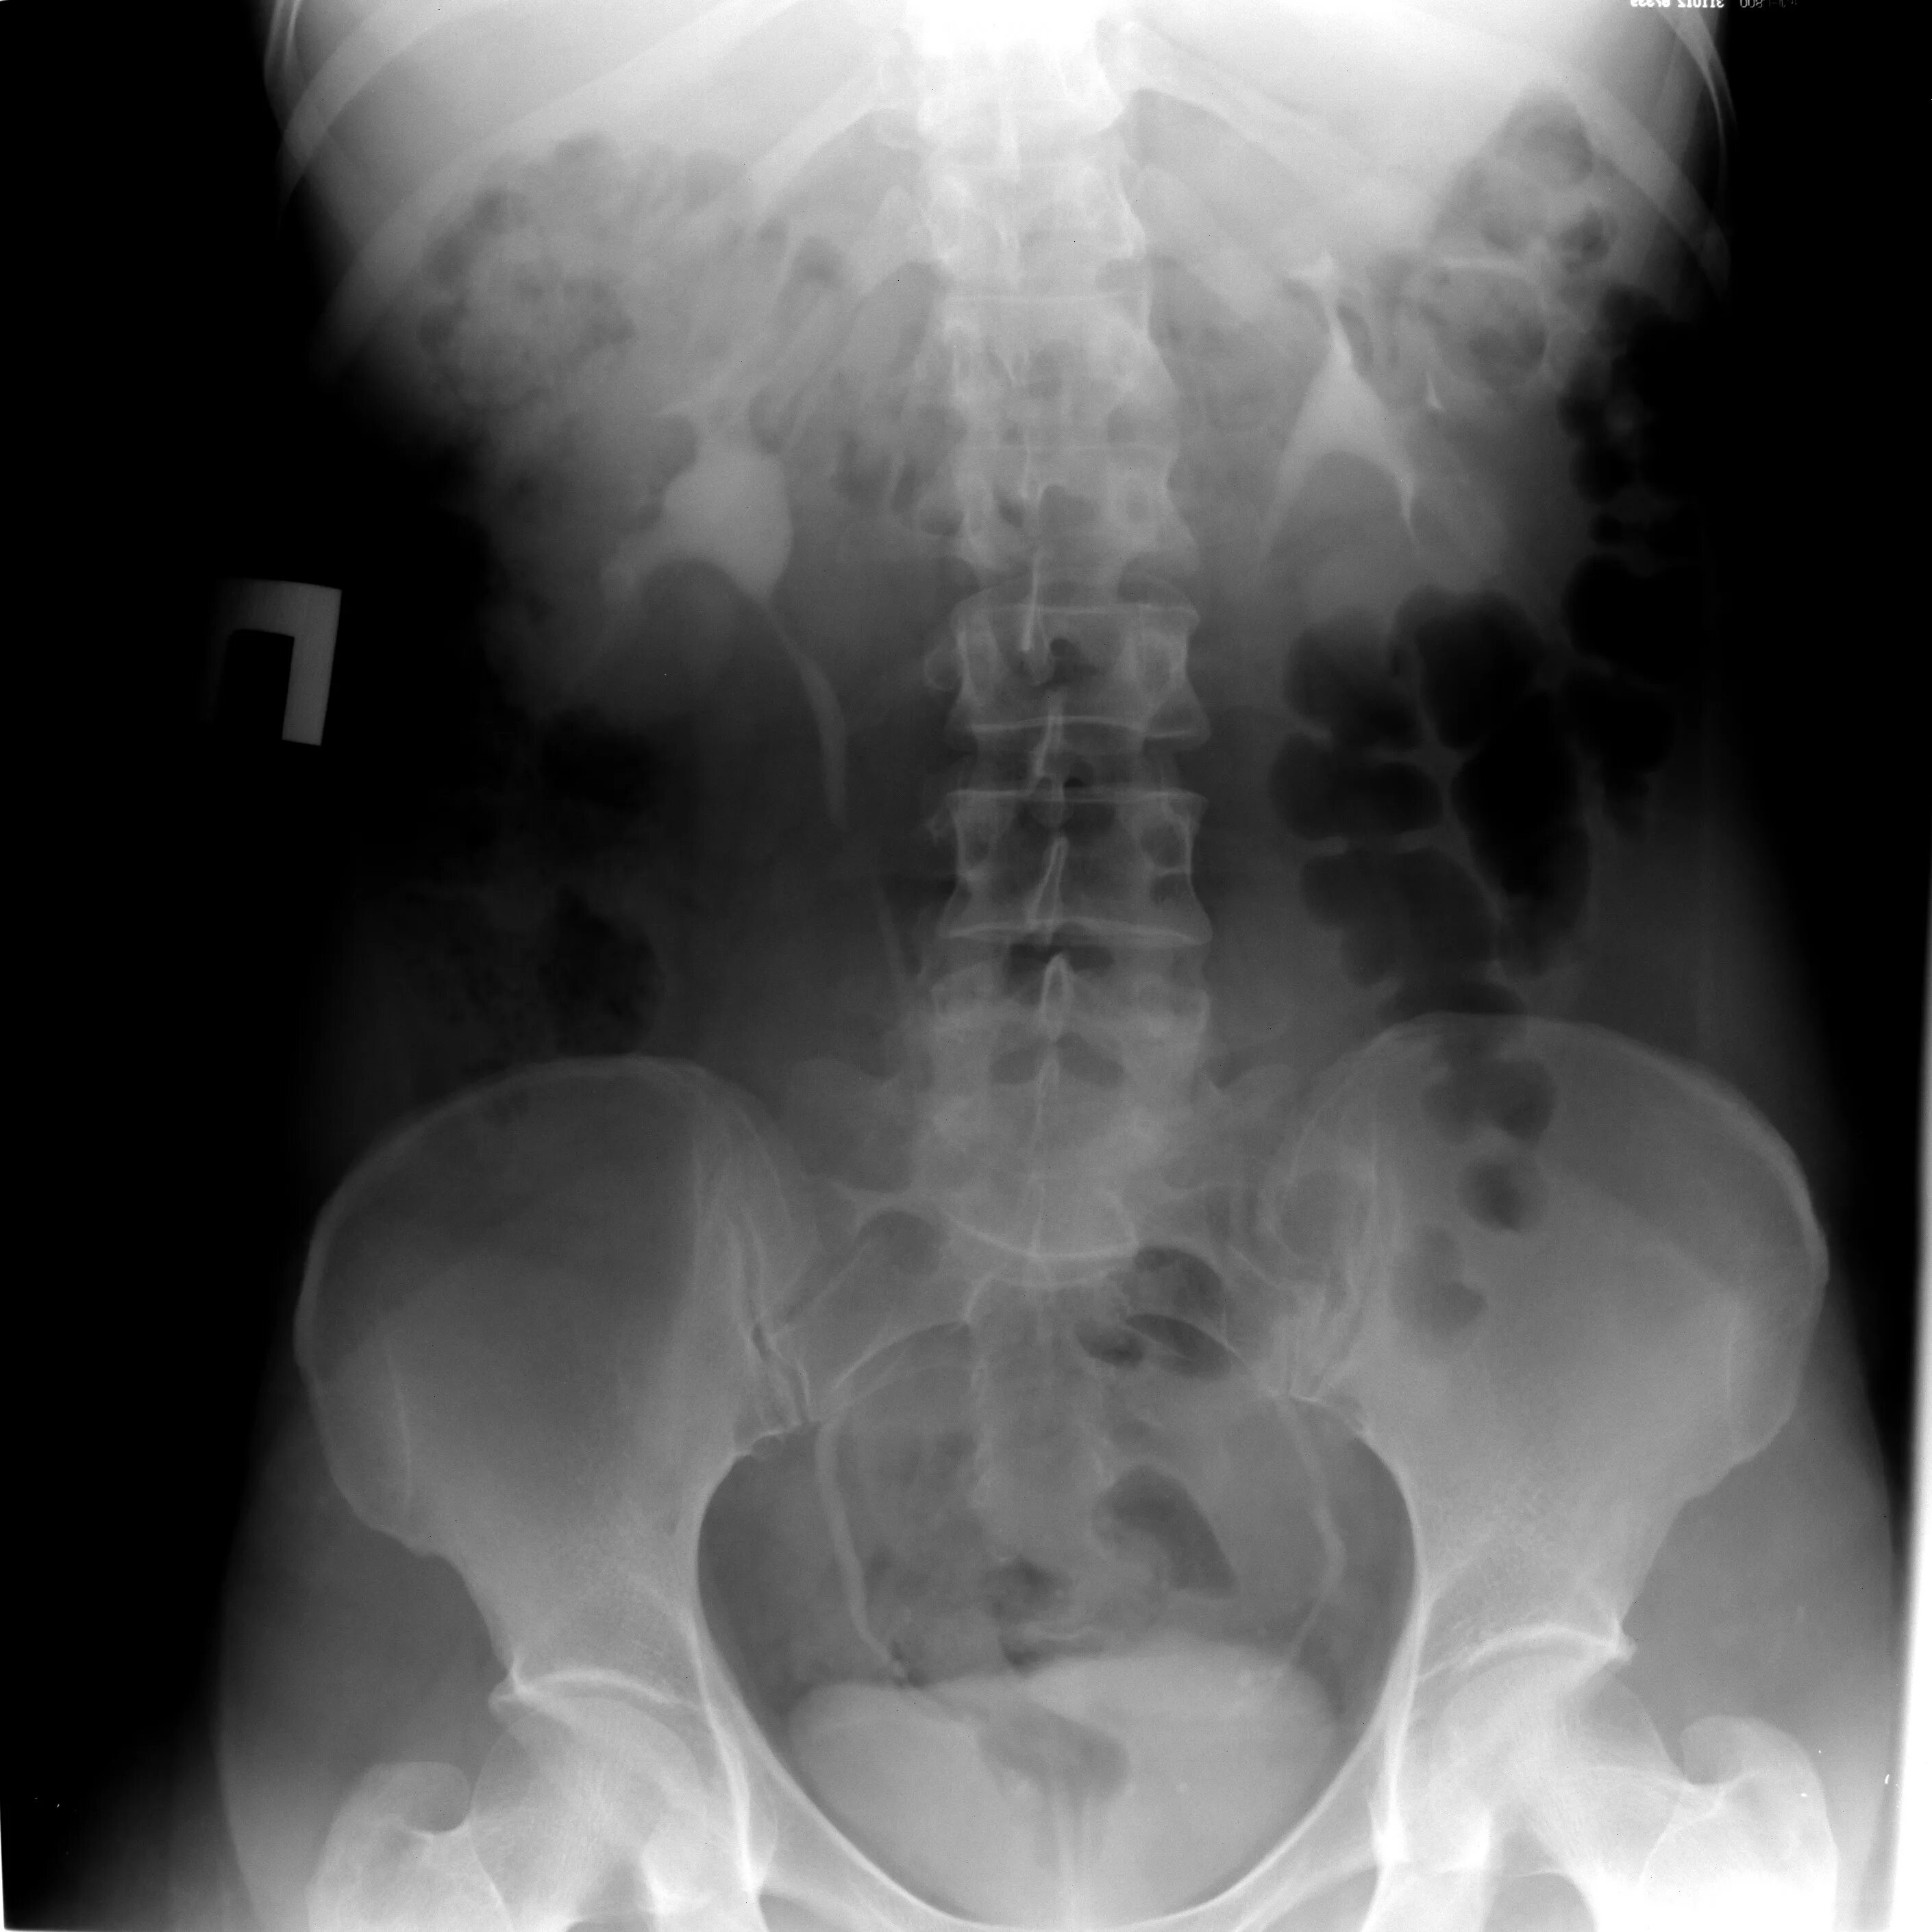

После урографии